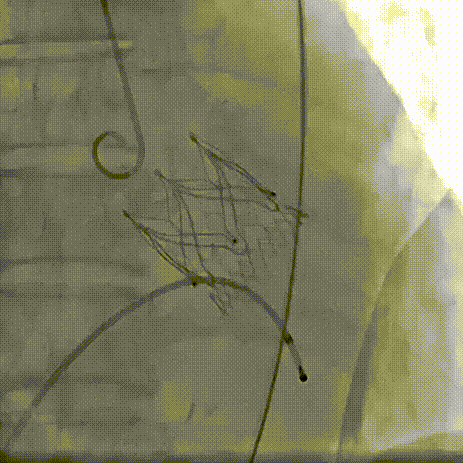

2026年伊始,TaurusTrio经导管主动脉瓣系统在复旦大学附属中山医院,浙江大学医学院附属第二医院,中国医学科学院阜外医院,首都医科大学附属北京安贞医院,四川大学华西医院等多家临床中心成功开展上市后全国首批植入。这不仅是TaurusTrio正式走向广泛临床应用的重要里程碑,更标志着中国单纯主动脉瓣反流介入治疗正式迈入了“心键合璧”的全新纪元。